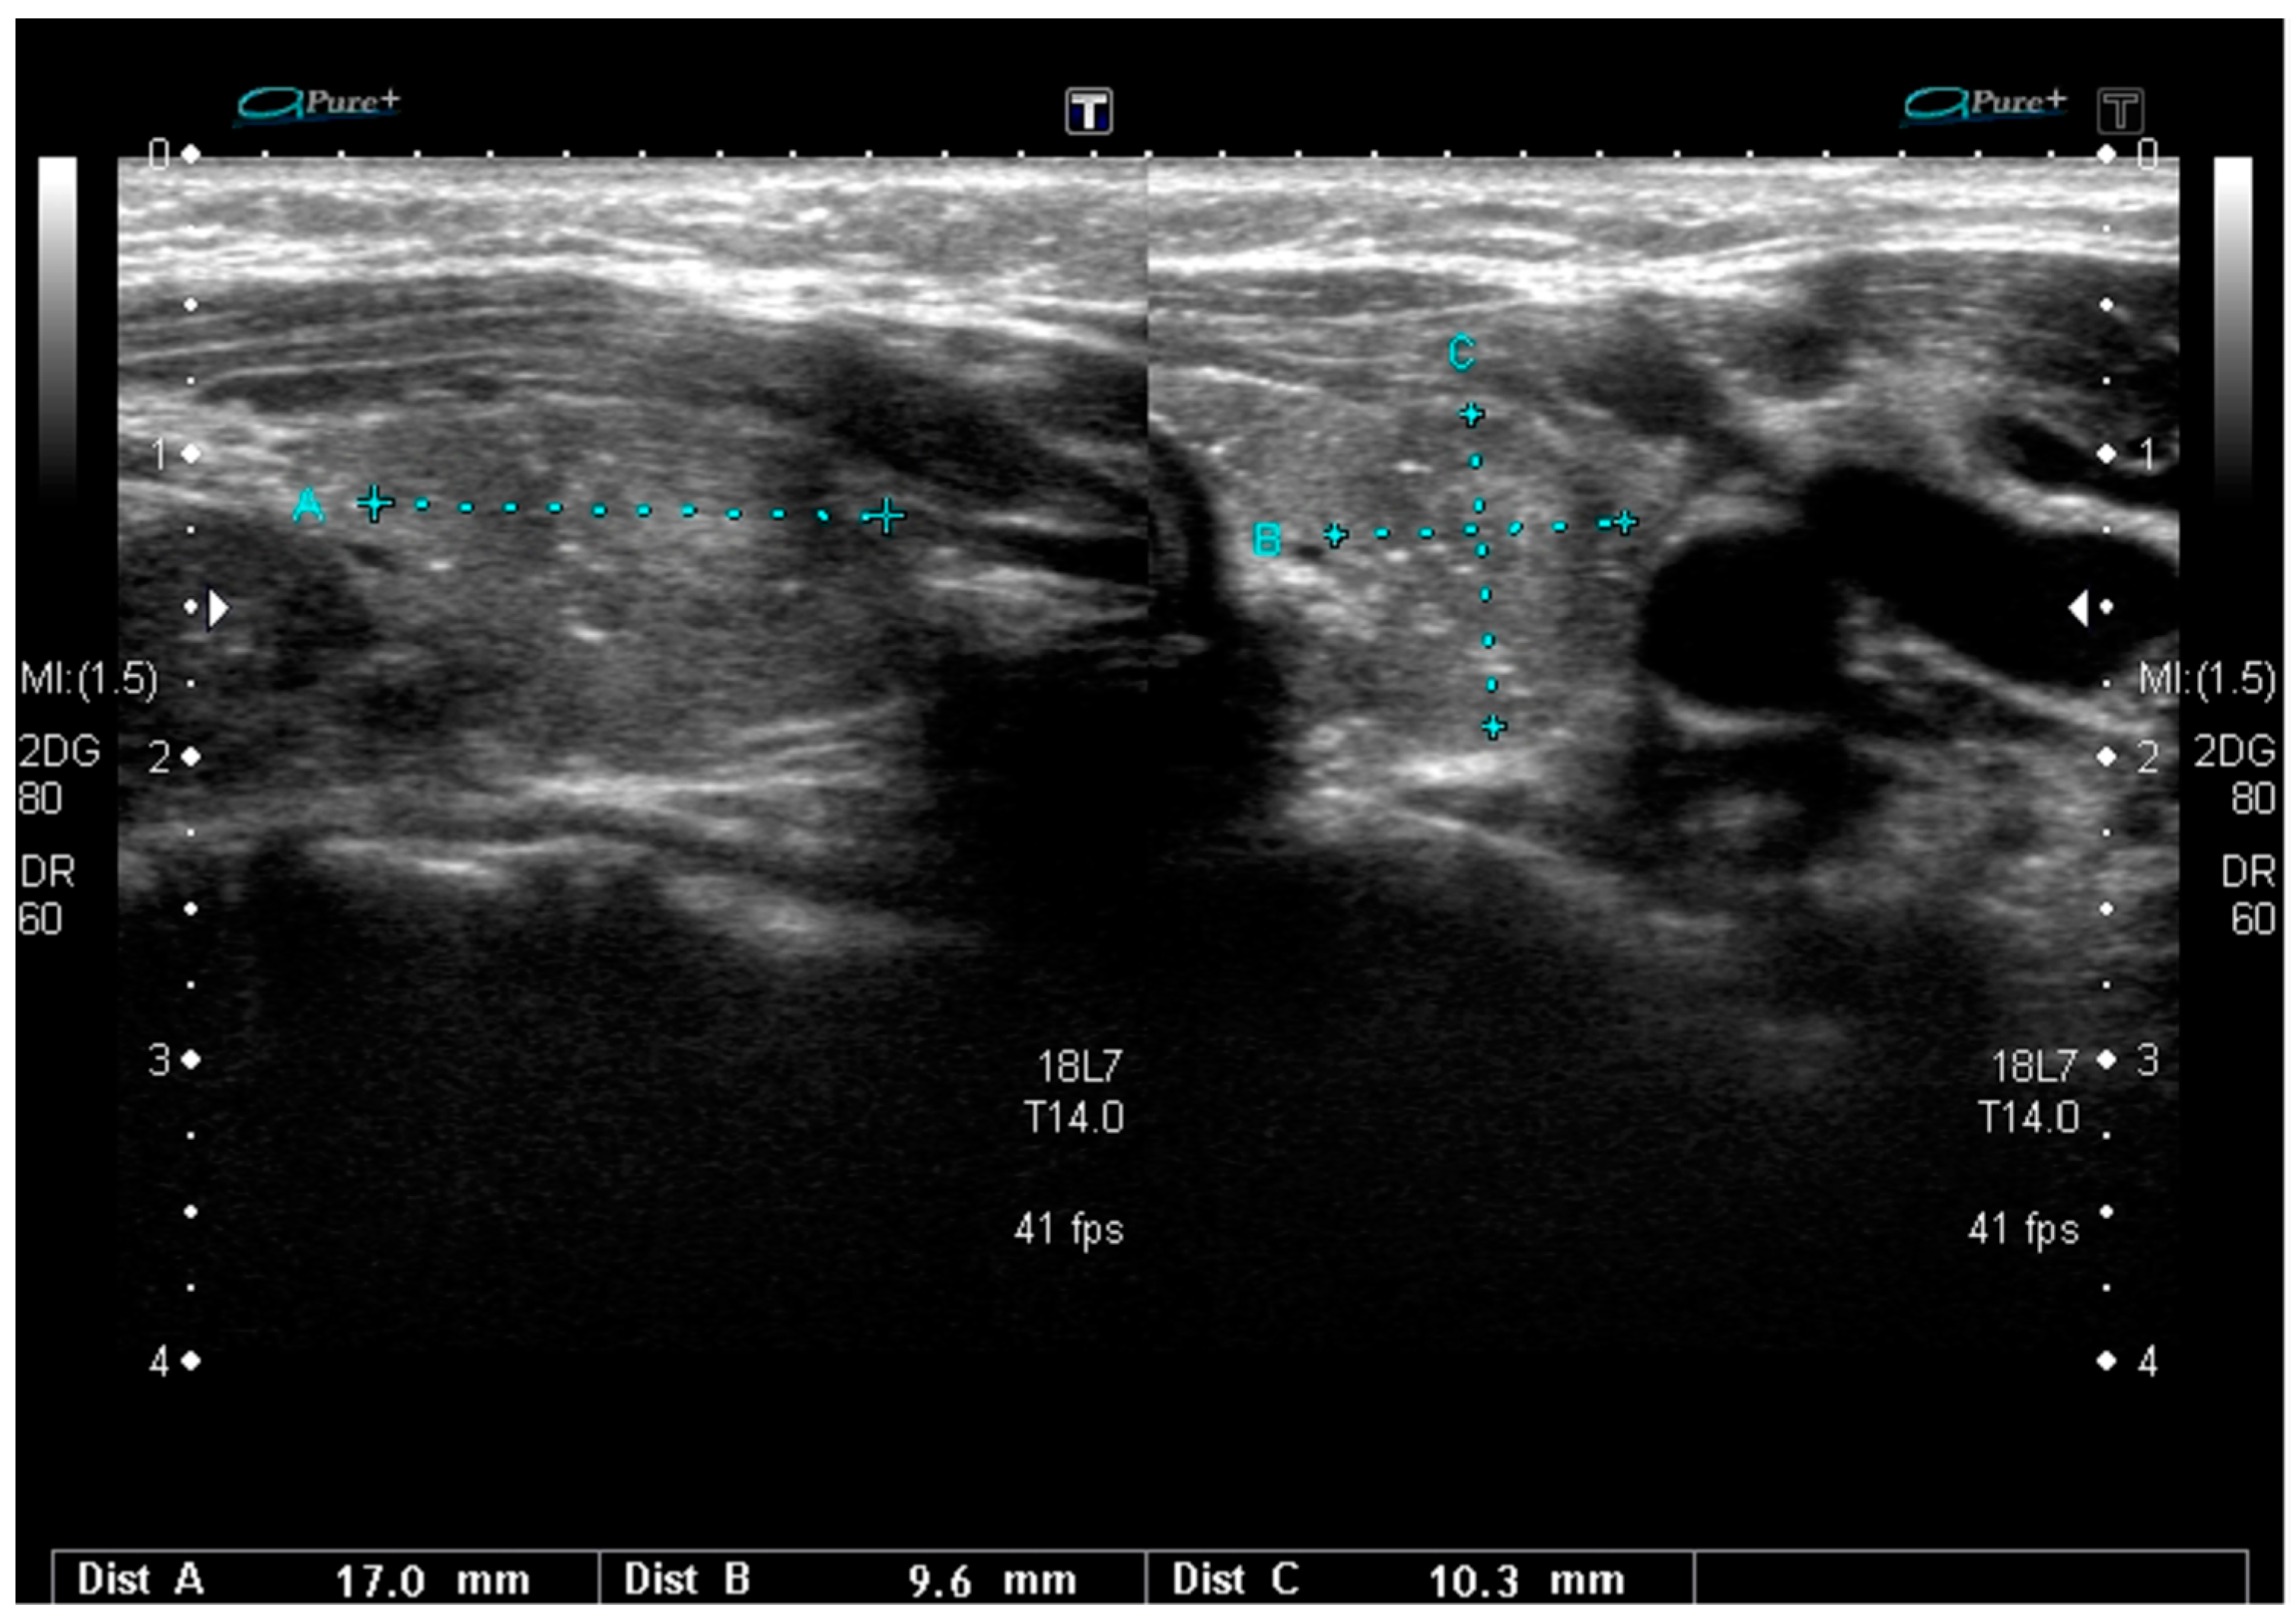

According to the 2017 WHO classification, two subtypes of FV PTC are distinguished: Invasive encapsulated FV PTC (i.e., the encapsulated FV with capsular or vascular invasion), and infiltrative FV, which is not encapsulated []. Invasive EFV PTC is associated with RAS mutation or PAX8-PPARγ and it constitutes 4% of all PTCs. Infiltrative FV accounts for 6% of all PTCs and is mainly caused by BRAF mutation, usually BRAFK601E, or, less often, RAS mutation [,,,]. BRAF mutations are therefore typical for the more aggressive infiltrative FV PTC while RAS mutations are often found in the less aggressive invasive EFV or the above-described NIFTP. US features of FV can suggest the tumor behavior and molecular landscape, as it can have typical PTC-like US patterns with hypoechoic lesions with irregular blurred margins and, sometimes, microcalcifications or rather follicular neoplasm-like patterns, without these markers of potential malignancy. Infiltrative FV is frequently a hypoechoic lesion, with spiculated/microlobulated margins. Microcalcifications can be present in about 20% of the cases. Nodules are often ovoid to round in shape, with a non-parallel orientation and mixed vascularization. The presence of microcalcifications is less common in the FV than in the classic variant of PTC (41.2% vs. 17.6%) [,]. Invasive encapsulated FV is typically a hypoechoic lesion with rather smooth margins and no calcifications. Nodule shape, orientation, and vascularity are similar to the infiltrative type of FV [,]. Similar observations concerning more benign US features of nodules harboring RAS mutations were presented by Rossi et al. [], who demonstrated that most of them were isoechoic. Nodules bearing RAS mutations were also larger than nodules with BRAFV600E mutations (>1 cm) []. Interestingly, de Napoli et al. [] observed microcalcifications and irregular margins in nodules with N-RAS mutation. US examination is a very good prognostic tool in examining follicular-patterned lesions with papillary nuclear features as the infiltrative FV PTC may be differentiated from the benign NIFTP on the basis of the US pattern. However, US-based discrimination between invasive EFVs and NIFTPs is rather impossible in clinical practice [,]. The presence of RAS mutations is usually associated with less aggressive forms of PTC and a more benign US image (Figure 4).

Figure 4.

Sonographic pattern of RAS-positive papillary thyroid carcinima, slightly hypoechoic, heterogeneous lesion with rather well-defined margins.